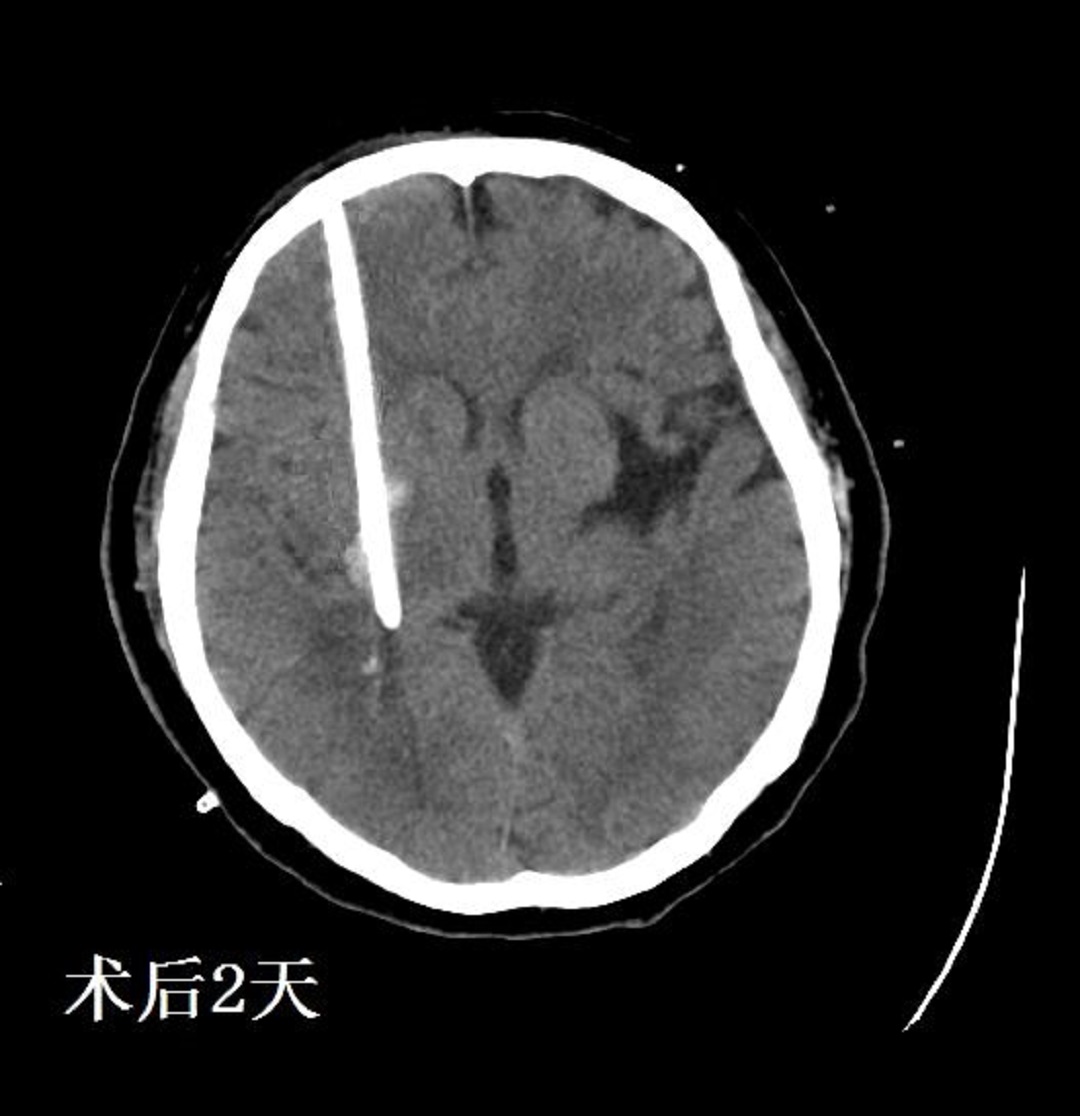

術(shù)后間斷注射尿激酶2萬單位,夾閉引流管3 h后開放,共注射四次,1天后復(fù)查頭顱CT,如下圖:

CT顯示血腫基本全部引出,患者意識恢復(fù)良好,拔去引流管,目前此患者已經(jīng)出院回家休養(yǎng)。